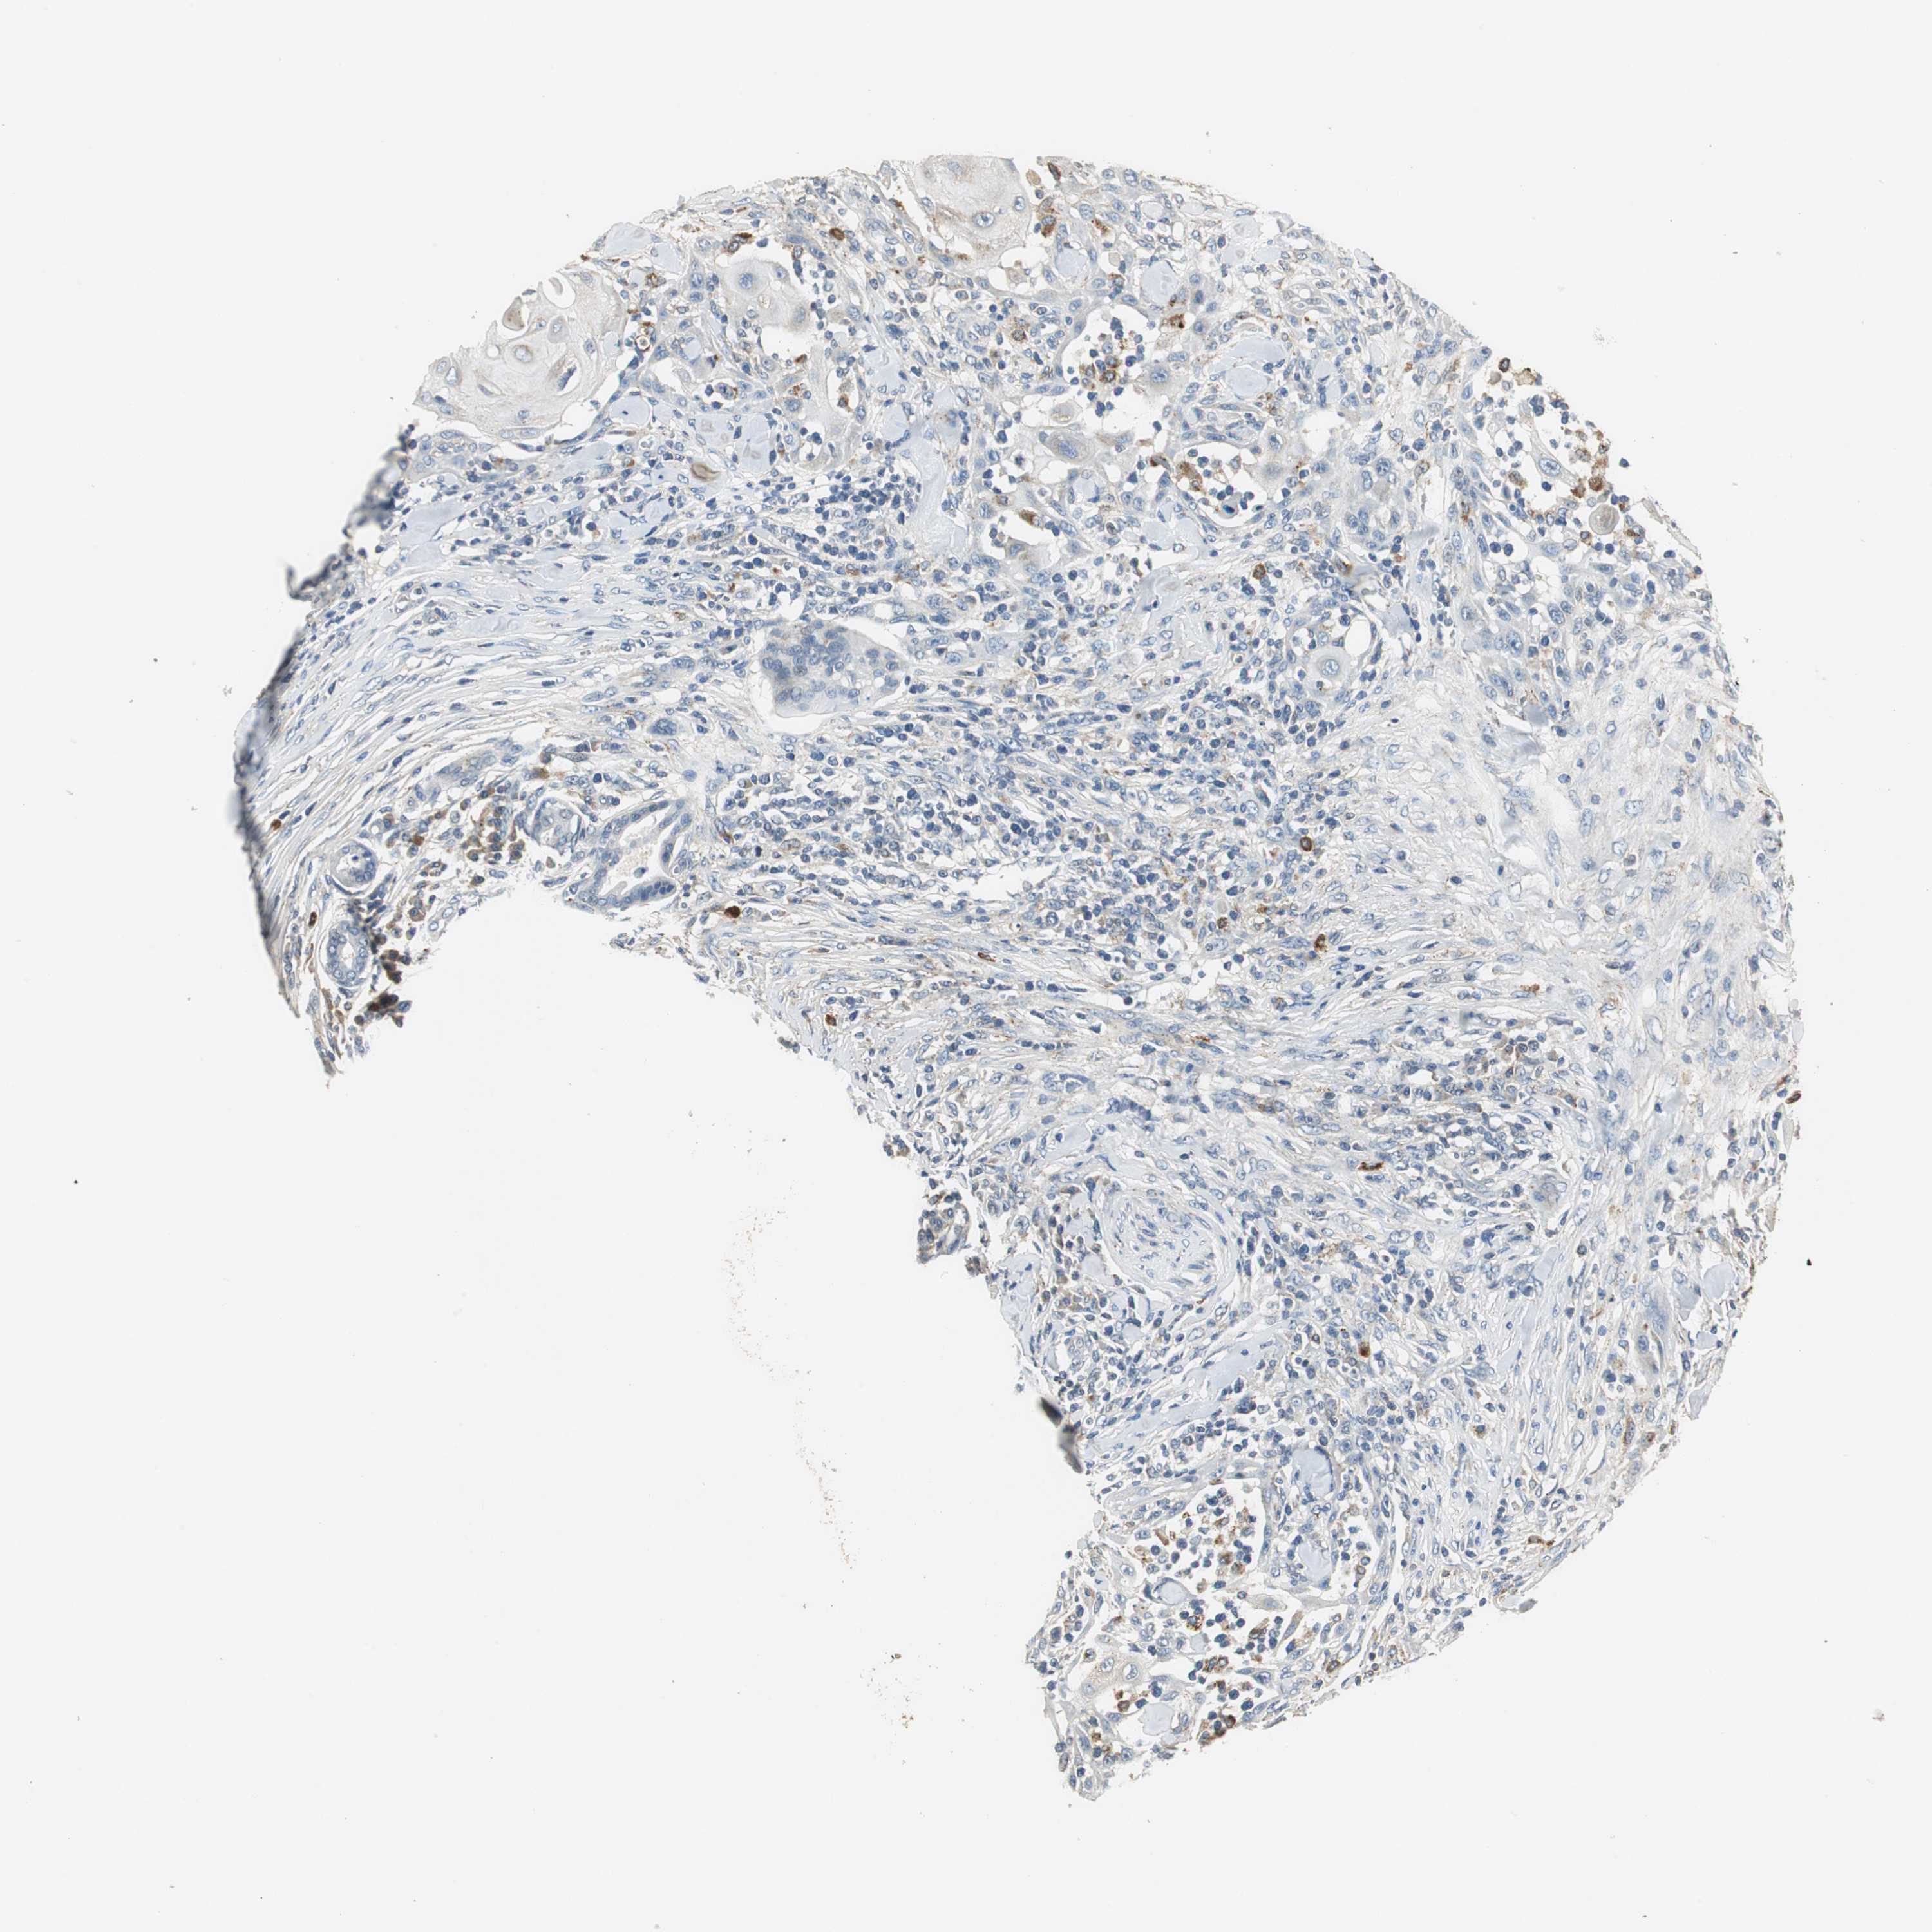

SKIN CANCER - Protein expressioni

A mouse-over function shows sample information and annotation data. Click on an image to view it in a full screen mode. Samples can be filtered based on level of antibody staining by selecting one or several of the following categories: high, medium, low and not detected. The assay and annotation is described here.

Antibody stainingi

Antibody staining in the annotated cell types in the current human tissue is reported as not detected, low, medium, or high, based on conventional immunohistochemistry profiling in selected tissues. This score is based on the combination of the staining intensity and fraction of stained cells.

Each image is clickable and will lead to virtual microscopy that enables deeper exploration of all samples and also displays staining intensity scores, fraction scores and subcellular localization as well as patient and tissue information for each sample.

Antibody HPA006657

Staining

High

Medium

Low

Not detected

Intensity

Strong

Moderate

Weak

Negative

Quantity

>75%

75%-25%

<25%

None

Location

Nuclear

Cytoplasmic/membranous

Cytoplasmic/membranous,nuclear

Squamous cell carcinoma, NOS

Basal cell carcinoma